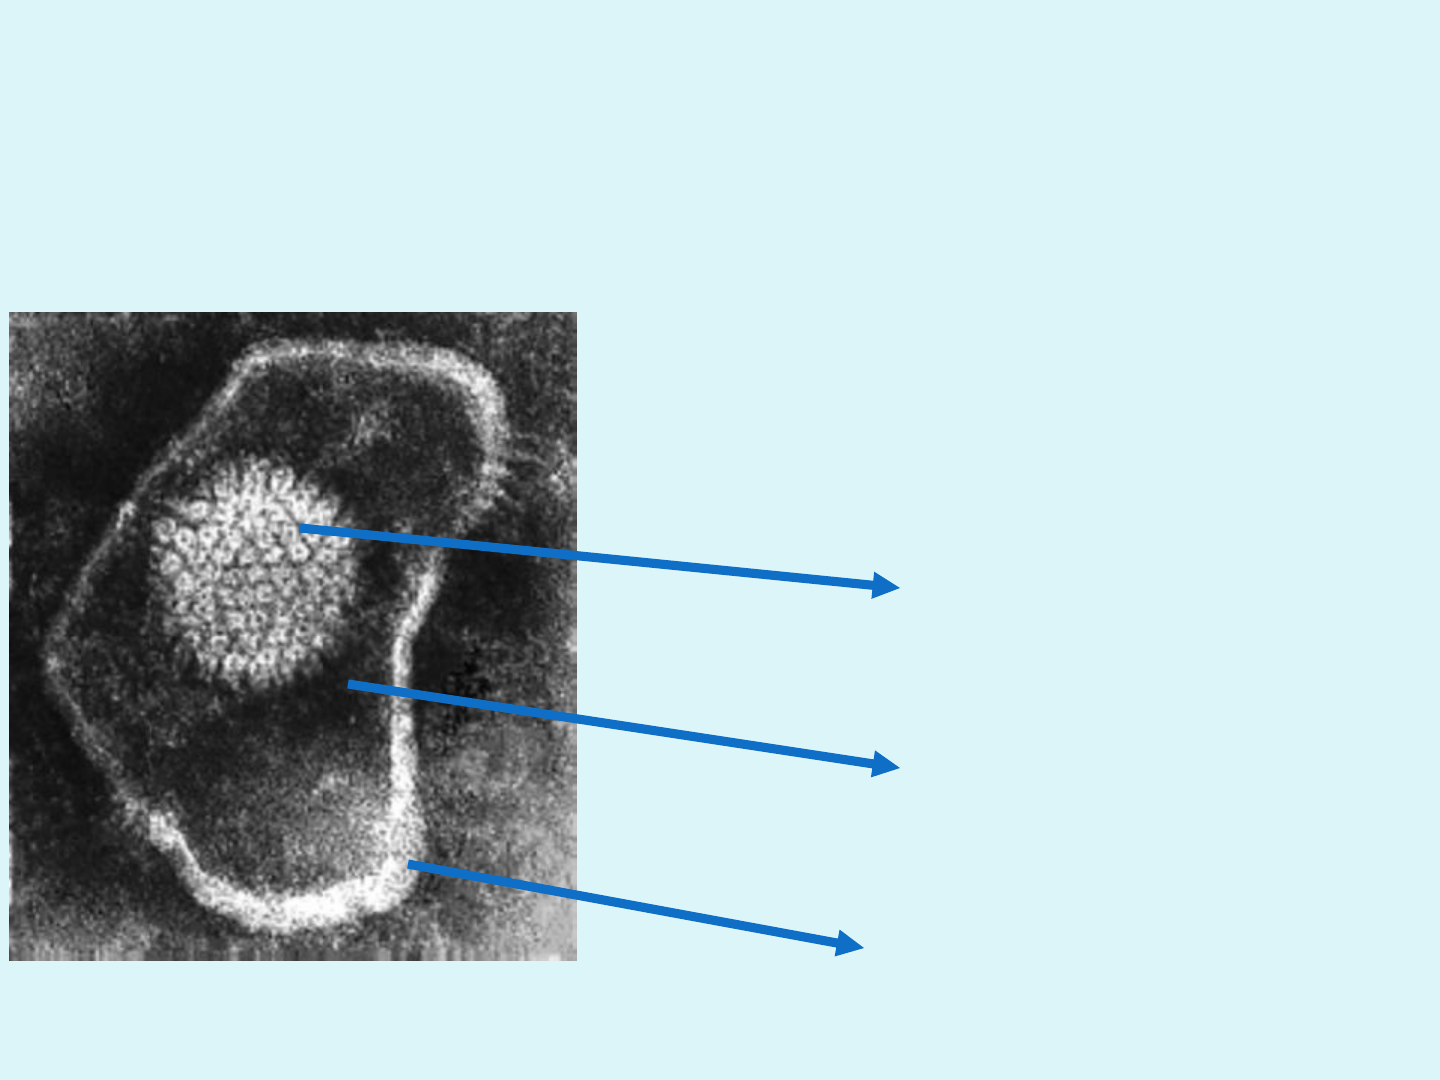

• Morfología: ME

• Estructura: Virus envueltos, genoma DNA de doble cadena.